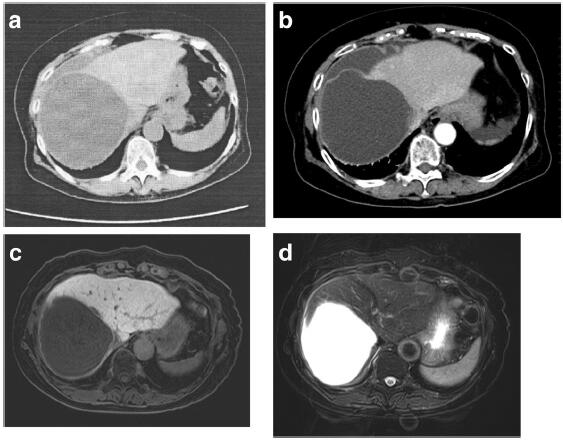

腹部 Mri 検査 嚢胞性腫瘍は多様な像を呈し A T1 強調像では嚢胞は概ね低信号で一 部が高信号 B T2 Download Scientific Diagram

腹部 Mri 検査 嚢胞性腫瘍は多様な像を呈し A T1 強調像では嚢胞は概ね低信号で一 部が高信号 B T2 Download Scientific Diagram

病案 选择性腹腔镜去顶术治疗自发性非寄生虫性肝囊肿破裂